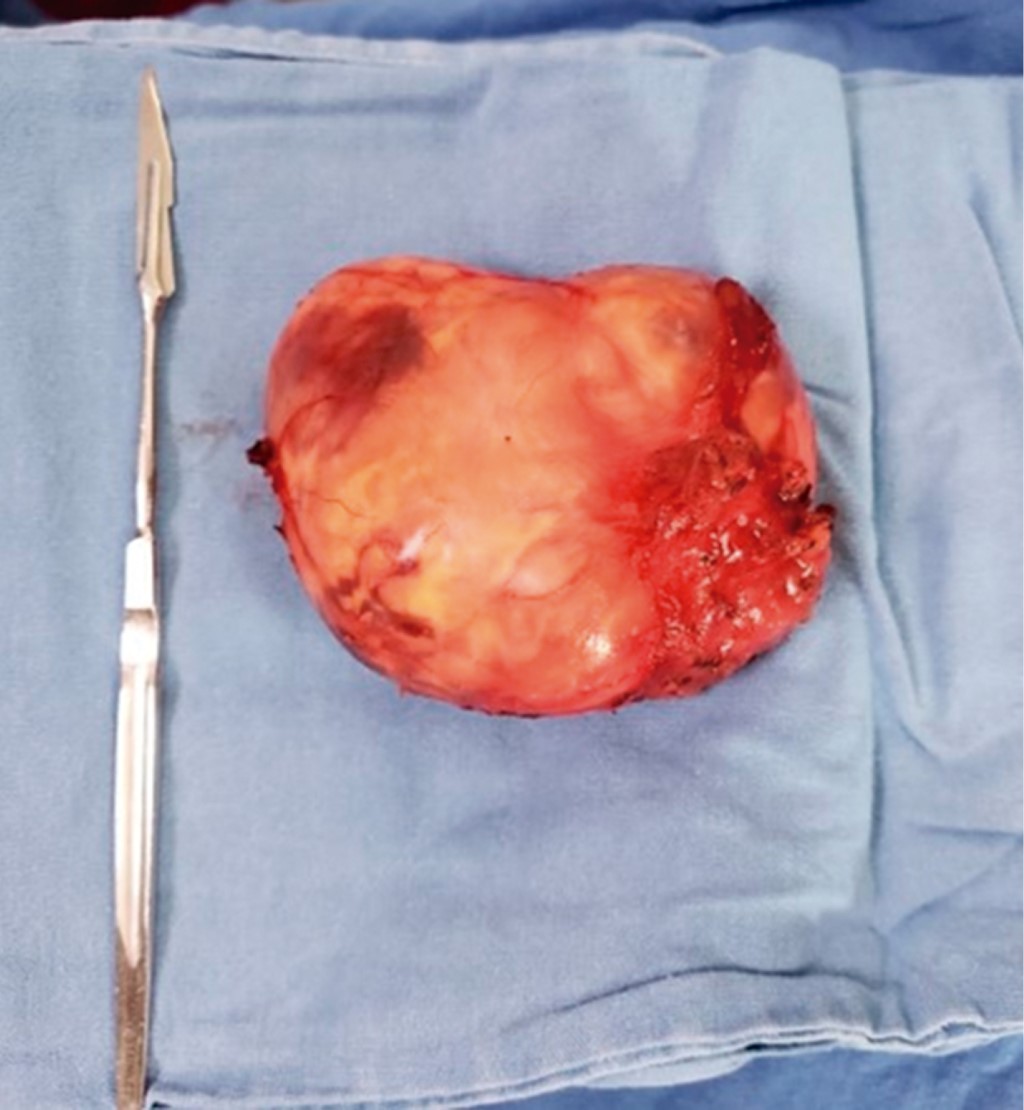

A la exploración física dirigida hay presencia de tumor cervical de 12 × 8 × 10 cm aproximadamente, indurada fija a planos profundos, que abarca región II, III y Va de hemicuello izquierdo (Figura 1), ligeramente dolorosa a la palpación 3/10 EVA, sin dificultad a la apertura bucal, sin datos de asimetría facial y sin compromiso de vía respiratoria.

Se hace protocolo de estudio y se programa para tiempo quirúrgico; en mesa de operaciones con paciente en decúbito supino con posición de Rossier se realiza cervicotomía mediante incisión cervical de Paul André, disecando por planos (piel, tejido celular subcutáneo, platisma) ubicando músculo esternocleidomastoideo, el cual se refiere encontrando detrás del mismo una tumoración localizada en espacio parafaríngeo situada entre vena yugular interna y arteria carótida (Figura 5), la cual se diseca siendo enucleada, se realiza una meticulosa disección subcapsular buscando así preservar las funciones del nervio de origen aparente, el X par craneal, evitando la resección de éste. Dicha pieza es enviada a patología, se realiza hemostasia, se coloca drenaje cerrado de presión negativa tipo Drenovac de 1/8 y se cierra por planos cerrando fascia con Vicryl 2-0 y afrontando piel con nylon 3-0 punto intradérmico, dando por terminado evento quirúrgico.

Posteriormente se obtiene reporte histopatológico con folio Q215-2022 que da como resultado un tumor de cuello compatible con schwannoma, con un reporte de inmunohistoquímica con resultado que describe S100 difuso (+++/+++) vimentina positivo (+++/+++) (Figuras 6 y 7).

Figura 1